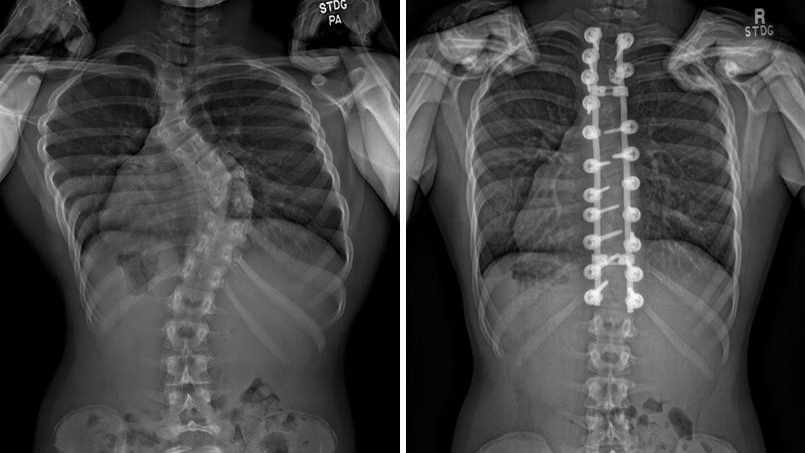

Scoliosis is a condition that causes the spine to curve. It often is diagnosed in children — perhaps during a growth spurt or in and around the time of puberty. However, it can be associated with other conditions such as arthritis, osteoporosis, infection or injuries to the spine. There are also other conditions, including congenital or neuromuscular diseases, that con contribute to a curvature.

Most people with scoliosis have a mild spinal curve that can be monitored by their healthcare team over time or treated with a back brace and physical therapy.